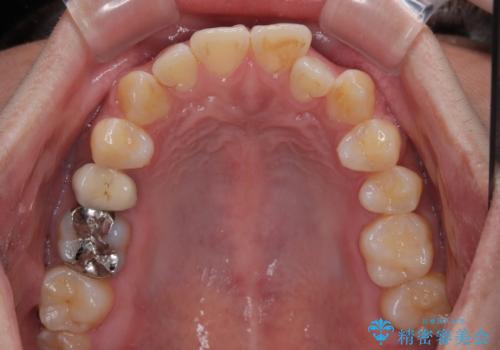

- 前歯の反対咬合などを気にして来院された患者様です。

ワイヤー矯正、マウスピース矯正どちらでも対応可能であったので、ご本人の希望によりインビザラインにて矯正治療を行うこととしました。

毎日の装着時間をしっかりと守ってくださり、1年強の短期間で、あっという間に治療を終えることができました。